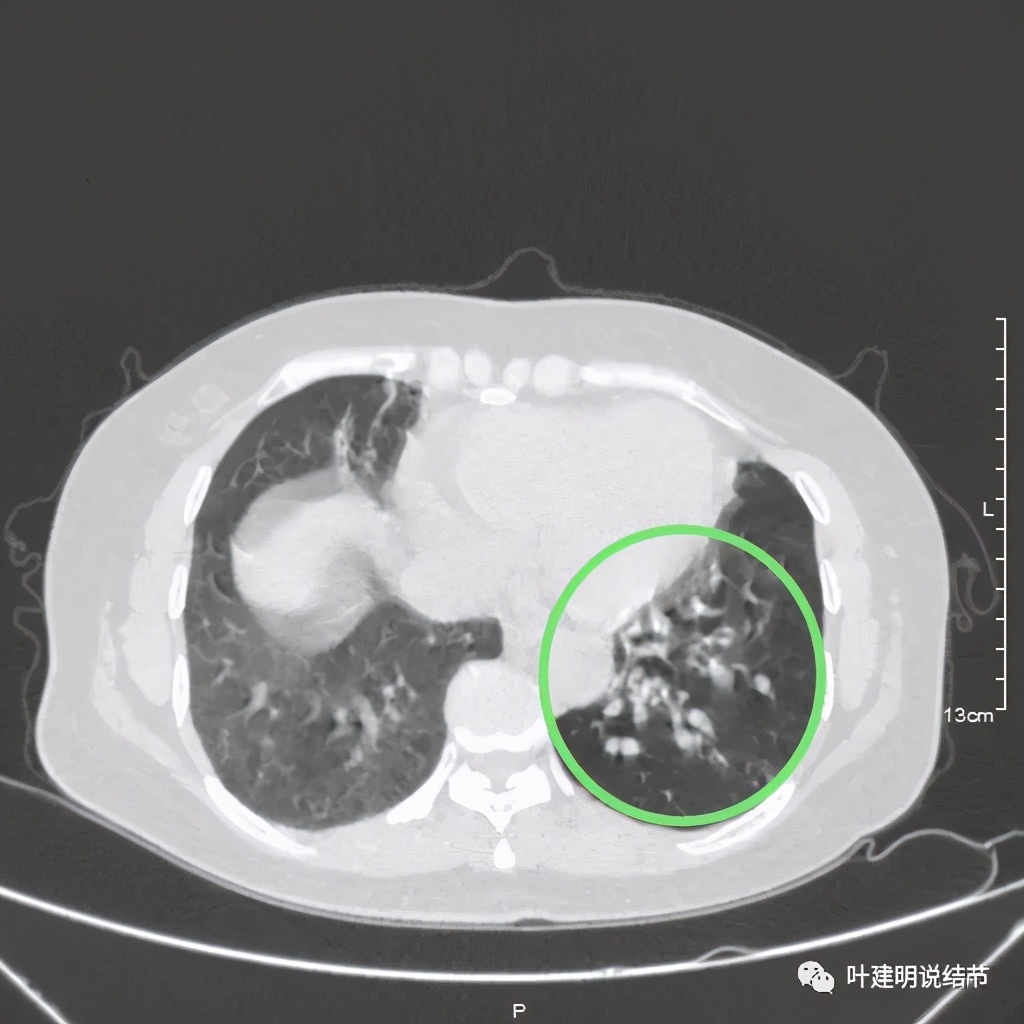

其实若从以上影像上看,恶性还真不能除外的,相对来说,恶性的可能应该大于良性。但看肺结节,我们在看细节特征的同时,还要看其他肺野有没有异常,综合来考虑。因为她的左下肺其他部位有病变存在,先来看下图像:

左下肺野多发支气管扩张呈囊状,也有一些实性密度的结节(考虑扩张支气管内的痰栓)。右侧也有实性炎性病灶。所以综合来看,左下之前的结节也得考虑与这些同源,一个原因来解释更为合理,所以恶性的可能性又小了。我建议其随访观察。昨天来复查,我们来看下这次的CT图像: